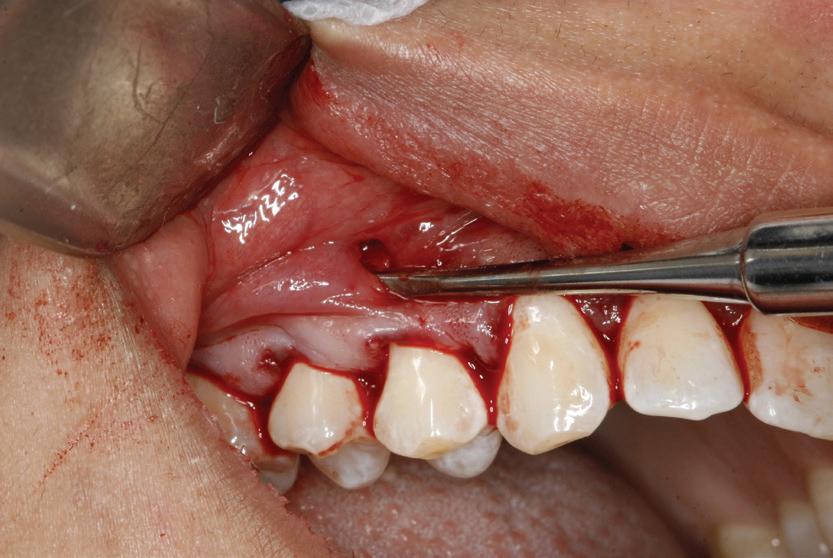

Lamboul repoziționat apical

Această tehnică este o opțiune atunci când nu există suficient țesut gingival keratinizat și este preferată atunci când caninul impactat este situat mezial față de incisivul lateral. Lamboul trebuie fixat și adaptat la dinte. Dezavantajele includ riscul de recesie și marginea gingivală neregulată, alături de necesitatea unei intervenții chirurgicale osoase extinse. Se efectuează incizii verticale, iar lamboul este deplasat într-o direcție laterală sau apicală. Se recomandă un design al lamboului în care baza și zona coronară sunt fie la aceeași lățime, fie mai înguste la bază, cu o grosime de 4-5 mm, astfel încât lamboul să fie suficient de lat meziodistal, extinzându-se cu 1,5 mm dincolo de unghiul dintelui (fig. 6, 7).

Osul acoperitor trebuie îndepărtat cu chiuretă sau freză diamantată pentru a expune porțiunea liberă a coroanei. Lamboul se poziționează apoi la CEJ și se fixează cu suturi periostale pentru o stabilitate mai mare. În funcție de gradul de impactare a caninului, se poate plasa un pansament parodontal, astfel încât țesutul să nu se închidă. Bracketul este plasat fie în momentul procedurii, fie la 10 zile postoperator. Dacă respectivul canin este situat prea apical, se preferă tehnica închi-

să. În general, deplasarea ortodontică începe la 4-6 săptămâni după expunerea chirurgicală. Când foliculul ce înconjoară caninul este larg, incizia lamboului trebuie făcută peste limitele acestuia, pentru a permite adaptarea optimă a lamboului la coroană și os. Pentru a determina buna adaptare a lamboului, atunci când buza se mobilizează, acesta ar trebui să rămână staționar.